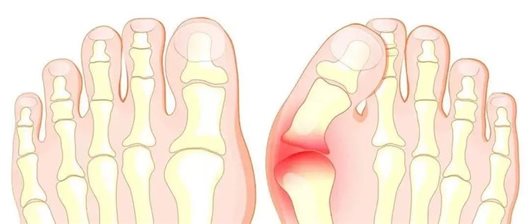

“芊芊玉足”是多少爱美人士的追求,然而拇外翻却让人们手“足”无措!苦不堪言!那么什么是拇外翻?

拇外翻俗称大脚骨、大骨拐、“大蛇头”,实际上是临床当中比较常见的一类前足畸形类的疾病,主要是指第一跖趾关节的拇趾向外侧偏移,引起来的一种足部畸形,通俗一点讲就是拇趾向脚外侧过度倾斜。该病是累及拇趾以及前足的最常见疾病。

畸形:拇外翻可引起足部其他部位的病变,如锤状趾、跖痛症、小趾滑囊炎、扁平足等。